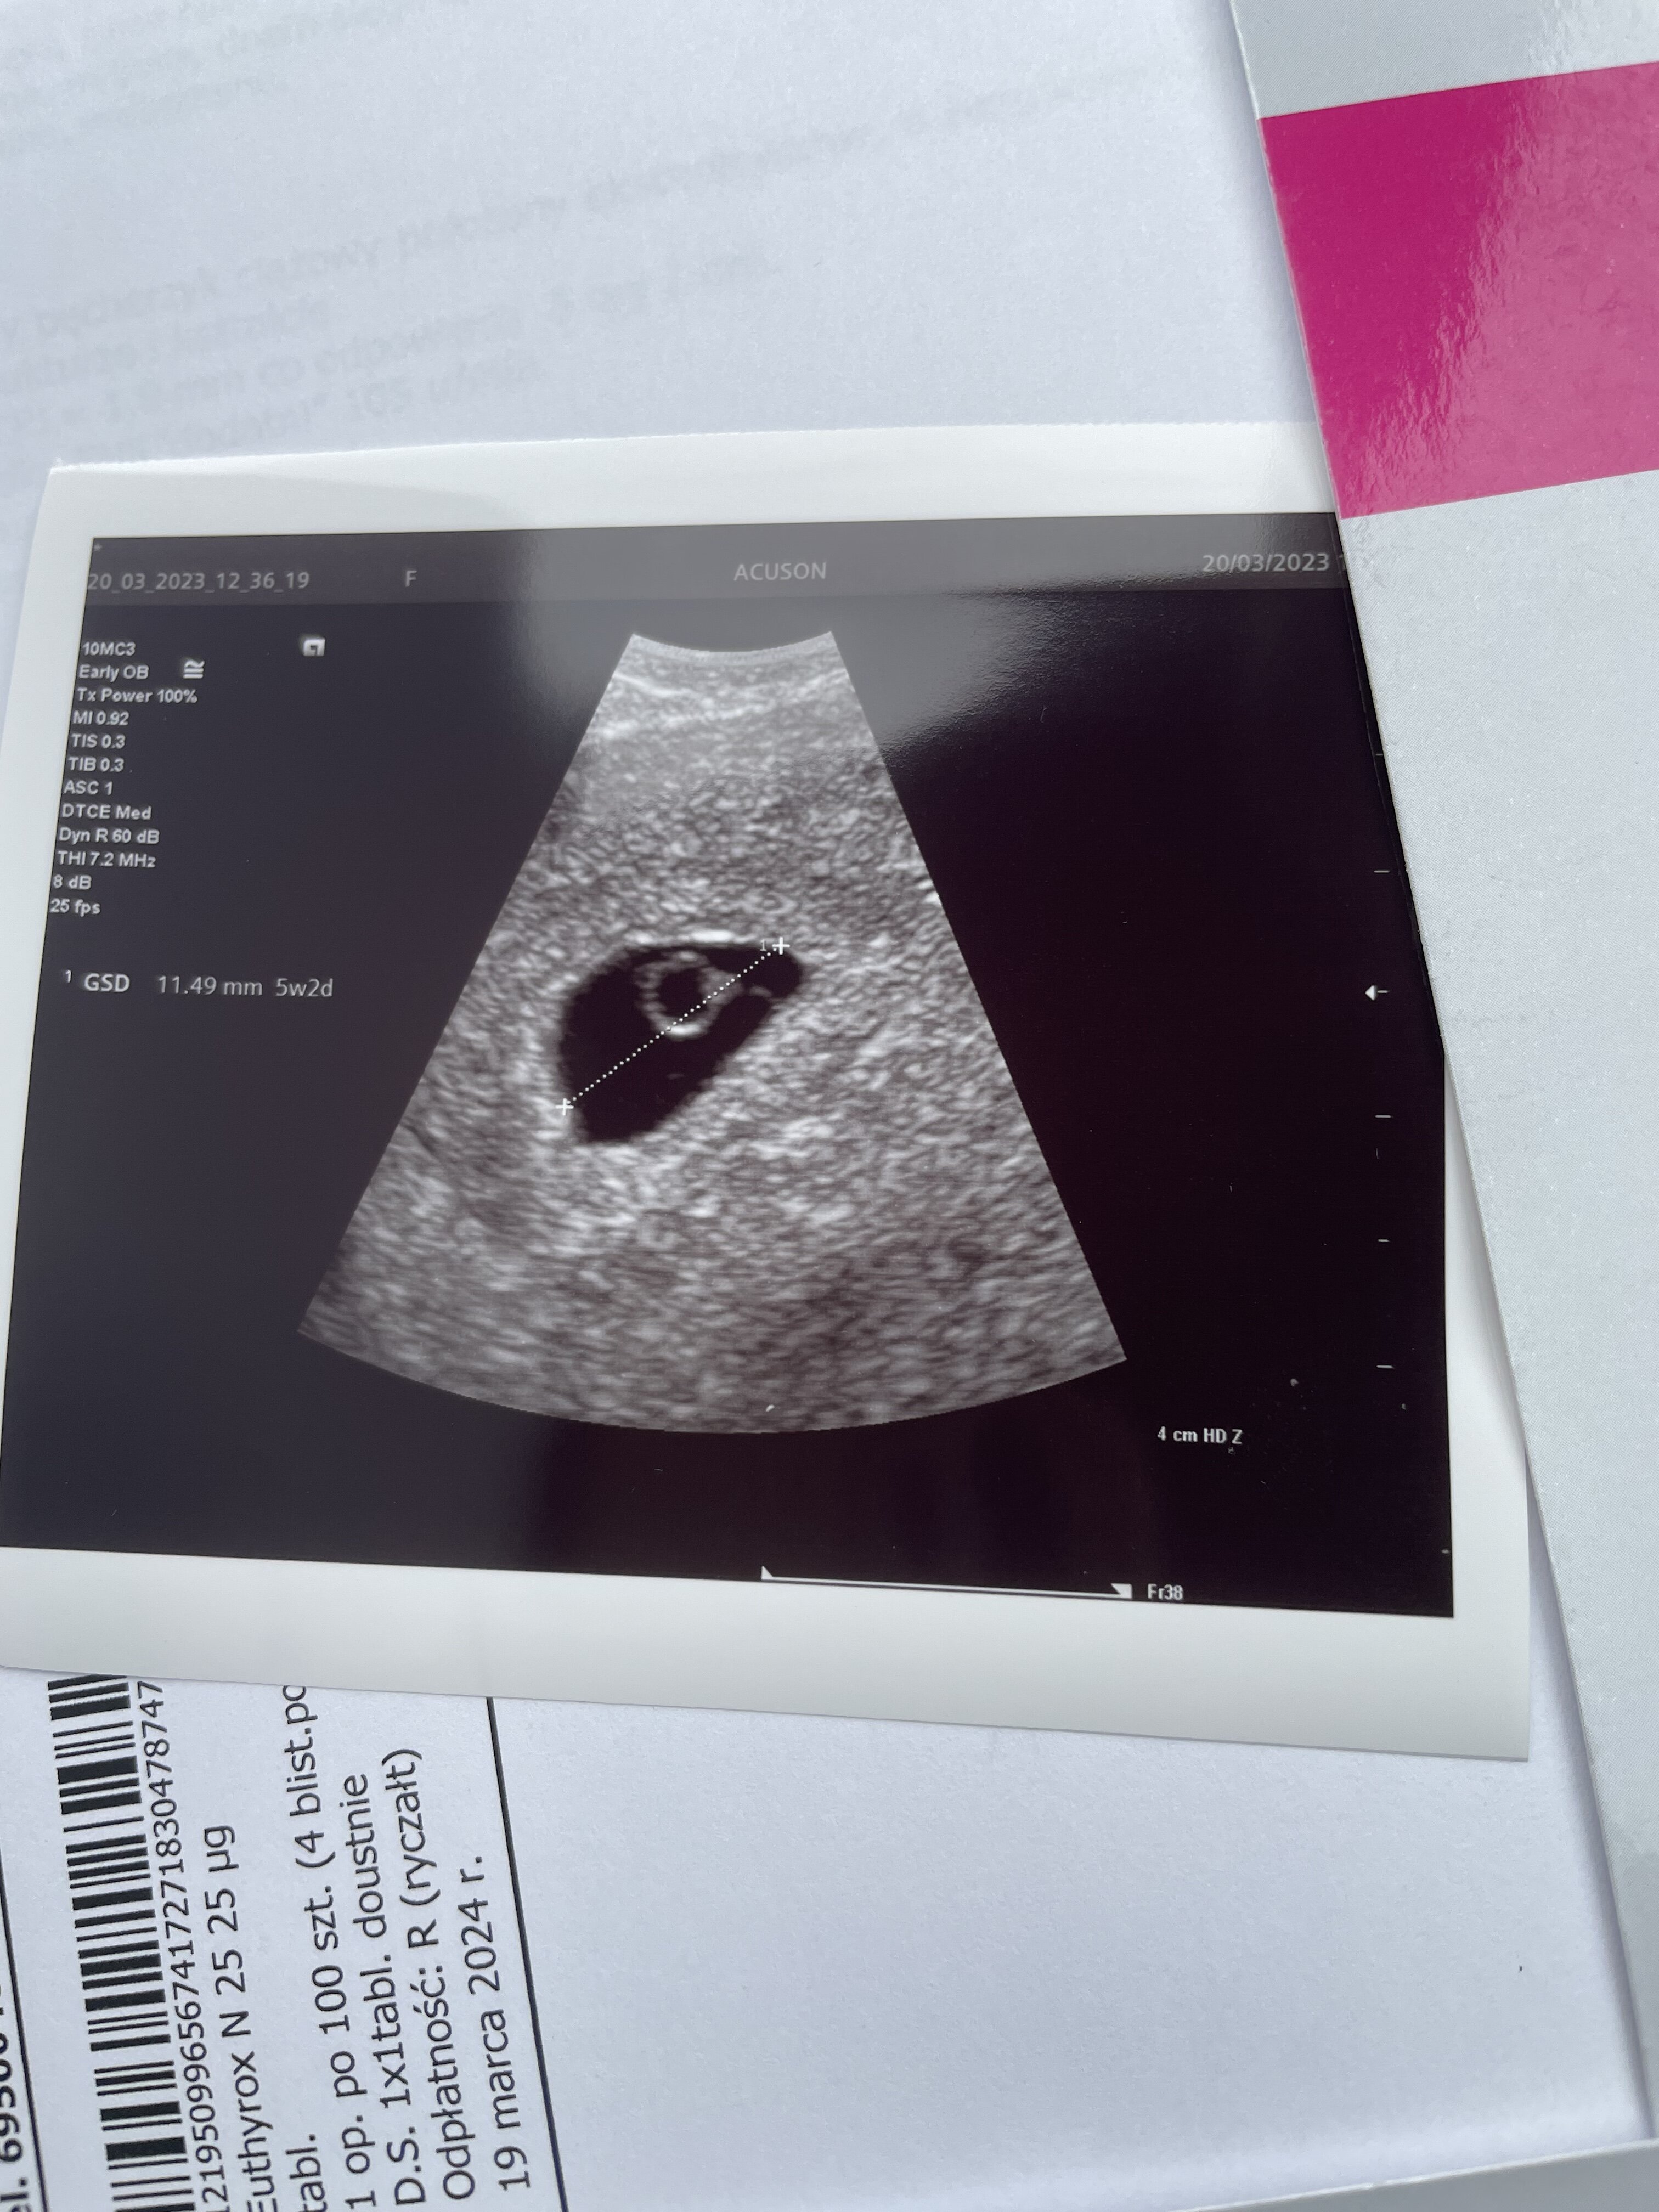

Jestem po wizycie . Serduszko jest widziałam jak bije ale jeszcze nie można go usłyszeć. Uderzenia prawidłowe. Wszystko jest okej.

Ciąża jest młodsza o 4 dni . Według OM 5+6 według USG 5+2.

Załączniki

• 60FE627C-B6CE-4099-90C9-51040A0A2FCC.jpeg

60FE627C-B6CE-4099-90C9-51040A0A2FCC.jpeg

1,3 MB · Wyświetleń: 134